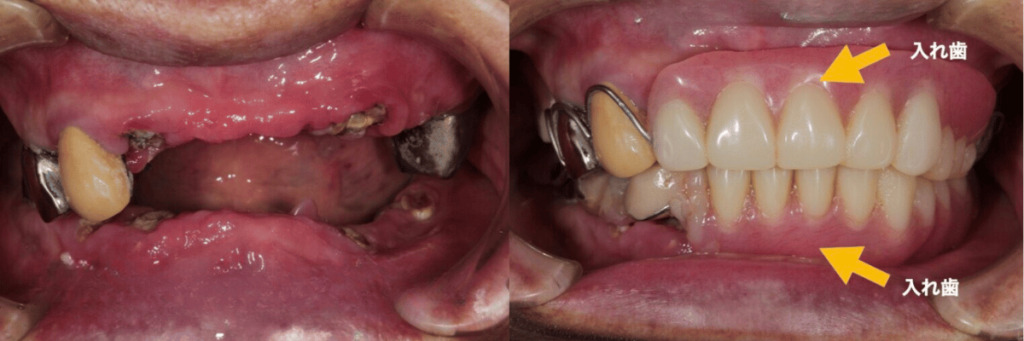

こちらの症例の患者様は、50歳を過ぎた頃から入れ歯を入れており、もともとインプラントをご希望でしたが、以前通っていた歯科医院では『あなたのお口の状態ではインプラントは難しい』と断られていたそうです。

当院に来院されたときには、折れたり歯茎に埋まってたりしている歯が11本もあり、残っている歯もすべて虫歯や根の膿で保存が難しい状態でした。

患者様は来院当時78歳でしたが、お身体は健康だったので、上顎8本と下顎6本のインプラントで、上下それぞれ12本ずつの人工歯を支えられるように設計しました。

折れた歯や歯茎に埋まっていた歯を全て除去し、歯周病治療なども終えたのちに最終の歯が入った際には、本当に喜んでいただけました。当時78歳とはいえまだまだお元気でしたので、しっかりと食事ができるようになりたいと強く思われていた患者様。術後には本当に何でも食べられるようになったと喜んでくださり、朝から焼肉を食べるほど食事を楽しんでいただいているそうです。